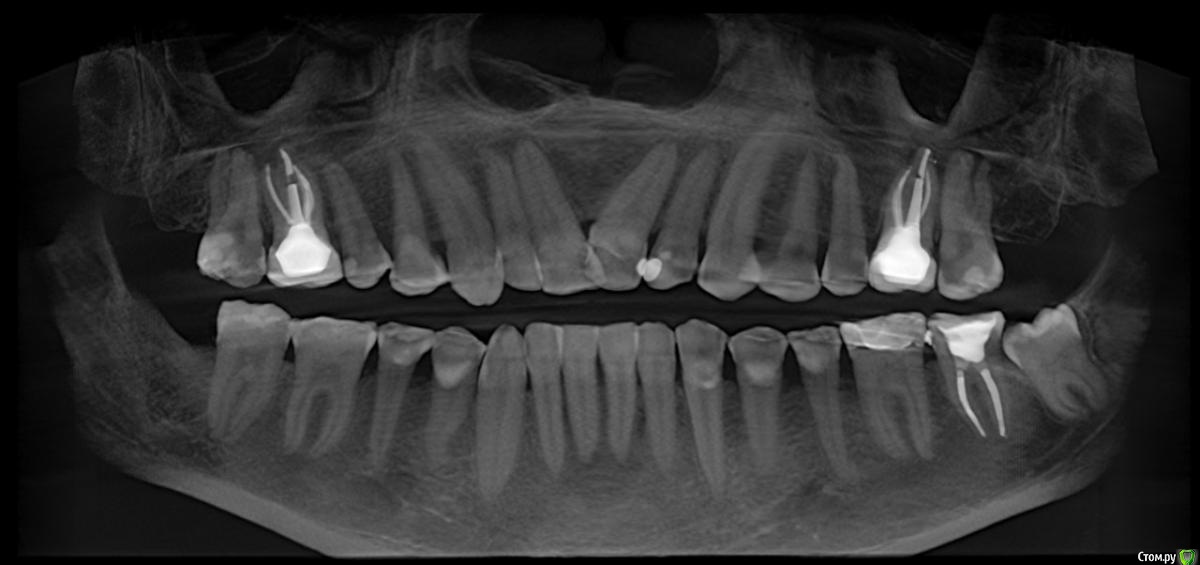

Этим летом занялся лечением, пролечили всё что можно, планировал выравнивать брекетами, остались вопросы, очень хочу попросить Вас посмотреть КТ и проконсультировать.

КТ (там и свежее и более старое -2017 года)

Удалены три зуба мудрости кроме слева снизу, слева снизу(6?) поставили вкладку-накладку, сверху и слева и справа(6?) поставили две вкладки и временные коронки на период брекетов.

2. Давно беспокоил передний справа зуб, вы еще на консультации говорили, что нужно ставить лекарство и ходить с ним... остальные врачи проигнорировали.. .Ортодонт посмотрел КТ и сказал никаких брекетов - за зубом киста, сказала идти к терапевту.

Прикладываю панораму, если я правильно ее вытянул из КТ ( кисту видно на фото во вложении в прошлом сообщении )